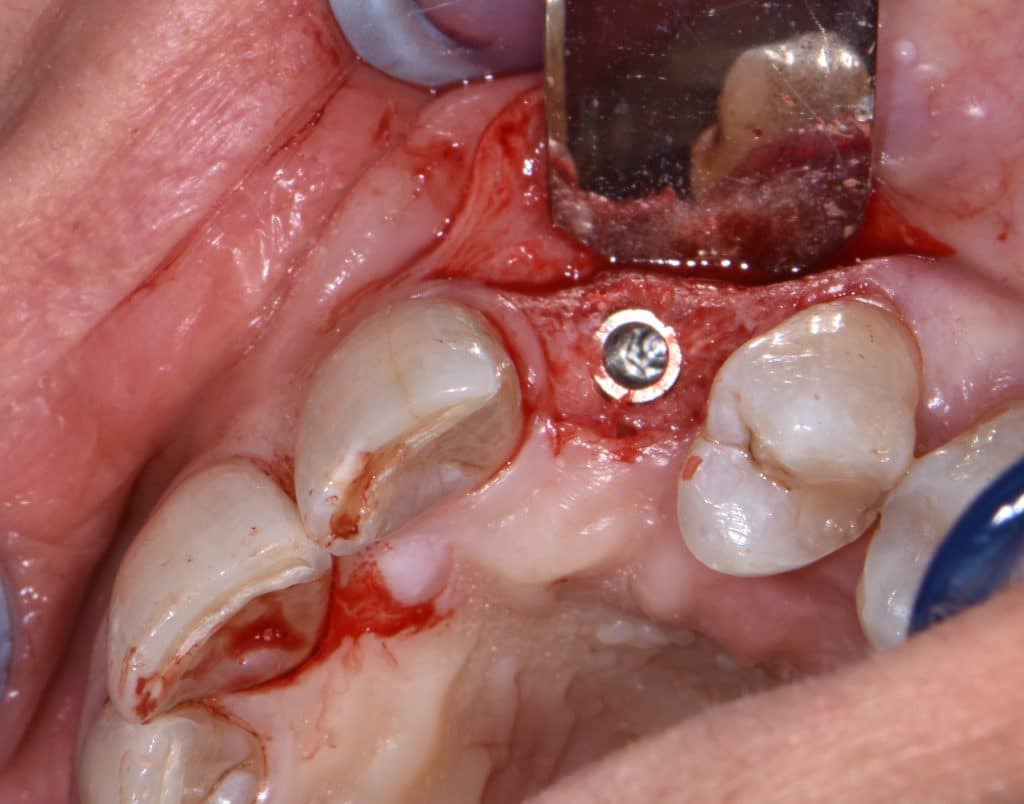

La pz N.G. di anni 52 (ASA 1) viene visitata nel mese di settembre 2017 per la mobilità ed inestetismo dell’elemento protesico 22, (foto iniziali sequenza 1) si evidenzia una frattura parziale della radice, si decide per l’estrazione ( foto sequenza 2) e sostituzione dell’elemento con un restauro implanto-protesico. Purtroppo la scarsa quota ossea apicale all’alveolo post-estrattivo (foto 2 rx) e l’alta valenza estetica dell’elemento ci rende cauti e si programma una socket preservation post estrattiva con l’ausilio delle membrane di prf (foto prf e socket sequenza 3 e 4). Durente i 5 mesi di guarigione la pz porta una protesi parziale mobile (foto 5,2) , a guarigione del sito post estrattivo si evidenzia una buona conservazione dei volumi osseo-gengivali,(foto guarigione sequenza 6) se pur presente una recessione distale all’elemnto 21.Nel mese di febbraio 2018 si procede all’inserimento di un impianto max-stability 3,75x12mm disegnando un lembo anticipato palatino per consentire un aumento dei tessuti vestibolari suturando con tecnica rool flap e trasformando l’elemento parziale mobile in una corona singola a carico immediato sul moncone temporameo applicando i concetti protesici bopt , (foto impianto moncone protesi provvisoria sequenza foto 7-8-9). Durante il periodo di maturazione dei tessuti molli vengono apportate opportune modifiche ai profili del provvisorio al fine di dare maggior spazio al tessuto gengivale, ( fotosequenza 10).Dopo circa 2 mesi dal protesizzazione provvisoria si è proceduto alla realizzazione del manufatto protesico con tecnica chair side sirona con l’ausilio del t-base (foto sequenza 11-12-13), realizzando in una sola seduta una corona in disilicato, ottenendo un risultato più che soddisfacente (Foto 14). Nel controllo a 3 mesi dal carico definitivo si apprezza la perfetta conservazione dei livelli ossei e gengivali. (foto sequenza 15).concludo con un follow up a 18 . Tengo a sottolineare che un caso come questo è stato conducibile con buoni risultati solo grazie alla piena fiducia della pz e alla sua massima motivazione e collaborazione. Ad oggi la pz sorride soddisfatta del risultato. E questo rappresenta la massima ricompensa di chi dedica tutto se stesso alla professione.